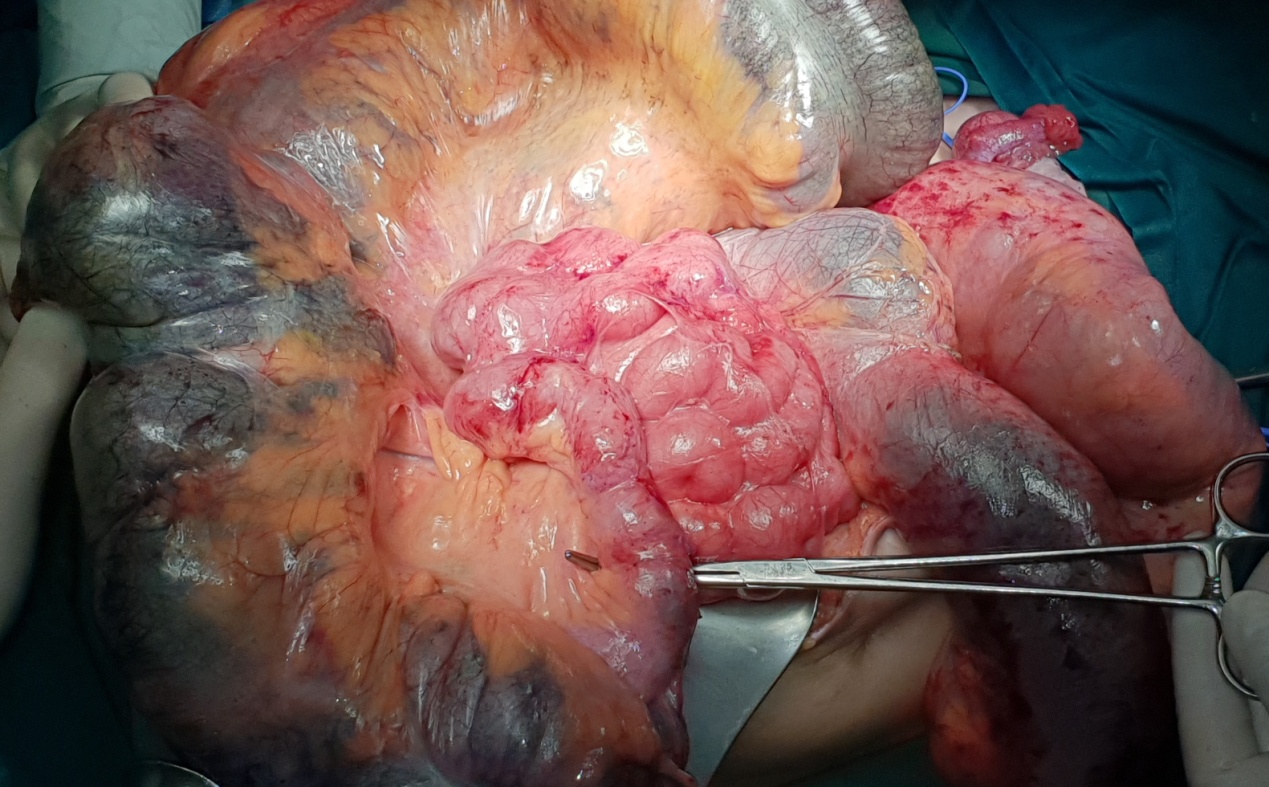

Καθολική γιγαντιαία διάταση ολόκληρου του κόλου (Ευγενική παραχώρηση Dr. V. Penopoulos)

Διερευνητική λαπαροτομία. Έντονη διάταση του κόλου (Ευγενική παραχώρηση Dr. V. Penopoulos)